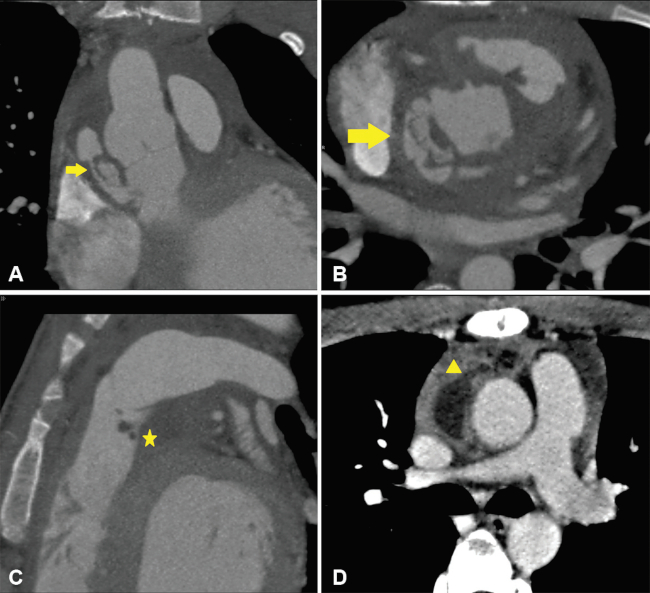

Aortitis sifilítica

La sífilis es una enfermedad sistémica de transmisión sexual causada por Treponema Pallidum. El estadio terciario de la enfermedad se manifiesta entre 5 y 30 años después de la infección primaria y se caracteriza por compromiso neurológico y cardiovascular (aortitis, aneurisma, valvulitis aórtica con regurgitación y estenosis de arterias coronarias).2 La invasión de la adventicia de la aorta causa endarteritis obliterante de la vasa vasorum, con el consecuente hipoflujo vascular, debilidad de la pared y formación de un aneurisma. Afecta la aorta ascendente en 60% de los casos y el cayado aórtico en 30% de los casos.1